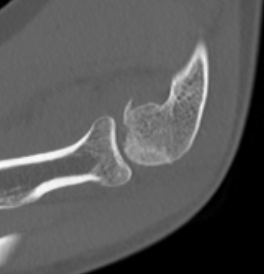

Coronal shear fracture of the distal humerus

Capitellum +/- trochlea

Operative management

Indication

Displaced fractures

- block flexion

- disrupt articular surface

Fixation

Headless compression screws AP / PA

Posterolateral plate

Lateral approach and ORIF

Technique

Arm on side table with tourniquet

- lateral approach centered on lateral epicondyle

- split extensor muscle

- open capsule and identify capitellum fracture

- reduce fracture

Usually AP headless compression screws (violates articular surface)

- +/- PA screws (risk AVN)

- +/- excise isolated cartilage lesions

- +/- postero-lateral plate